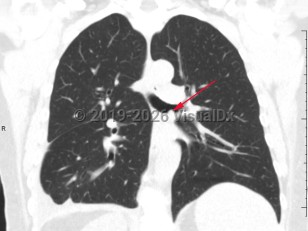

Fever, Cough, 50-59 year old Female

COVID-19

Viral pneumonia

Acute interstitial pneumoniaAcute interstitial pneumonia